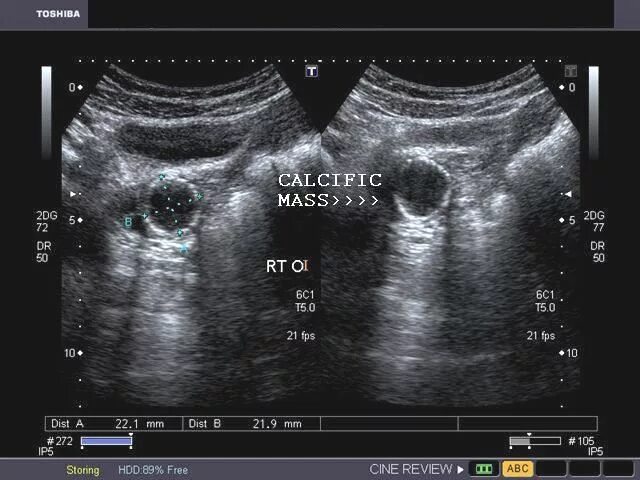

Кальцинат узи